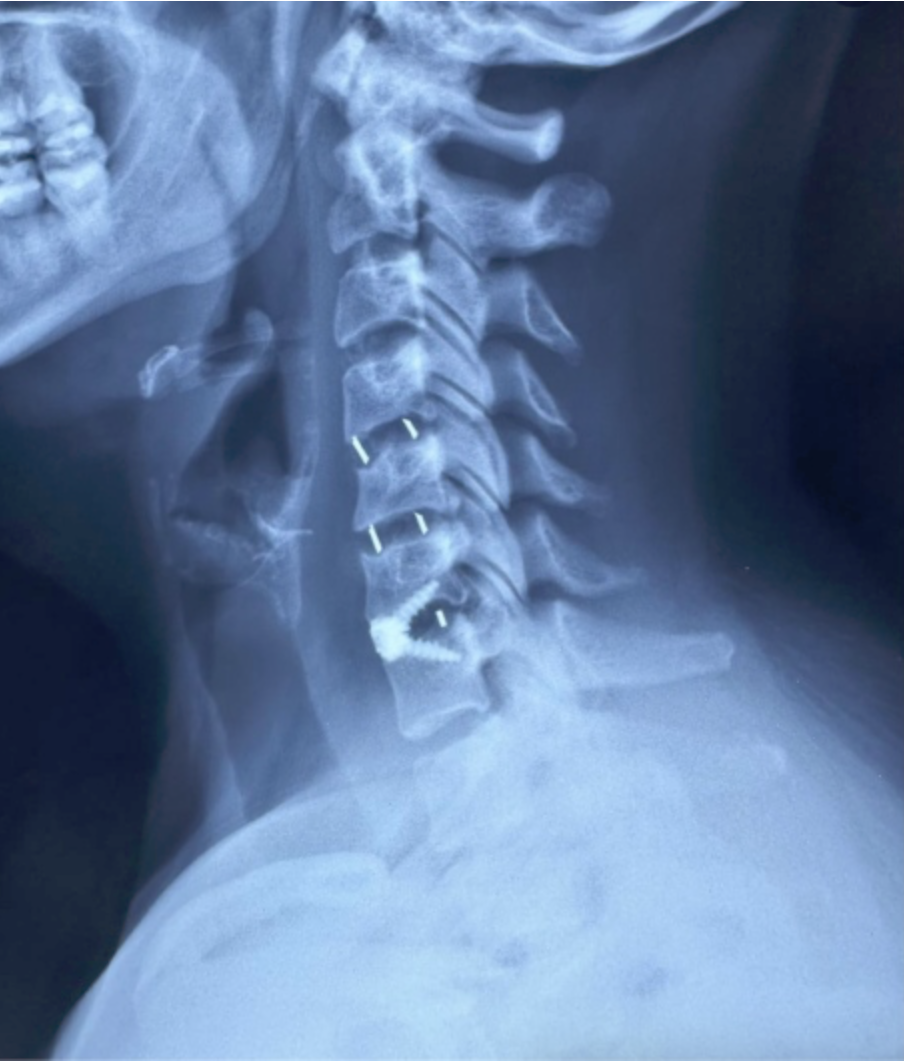

Cada procedimiento requiere una planificación detallada, basada en estudios de imagen y evaluación clínica, con el objetivo de lograr una descompresión adecuada de estructuras nerviosas y restaurar la estabilidad vertebral.

Se emplean técnicas quirúrgicas modernas, incluyendo abordajes mínimamente invasivos cuando son viables, lo que permite una recuperación más rápida y menor impacto en el paciente.